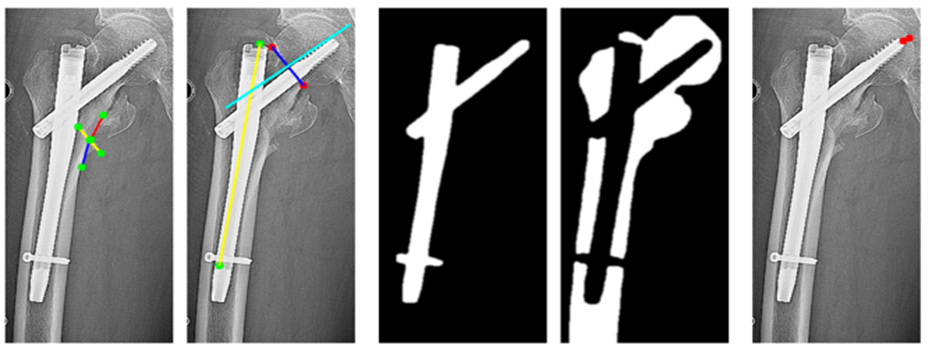

•基于Transformer大模型建立转子间骨折内固定失效的风险预测模型,实现对股骨颈干的精准分割、假体髓腔占比的计算、颈干角的计算及阴阳支撑的计算,完成预测模型的临床平台应用转化,为骨科手术提供量化依据